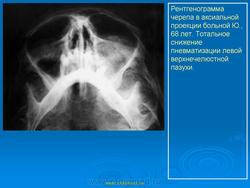

На верхней челюсти кисты встречаются в 2 раза чаще, чем на нижней. Кисты от верхних центральных резцов и клыков могут расти в сторону полости носа — при этом образуется выпячивание в полость нижнего носового хода или под нижнюю носовую раковину (симптом Gerber). Иногда может отмечаться рост в сторону твердого нёба, в этом случае на твердом нёбе появляется полушаровидное вздутие. Если рост кисты происходит в сторону верхнечелюстного синуса, наружных проявлений долгое время не отмечается. Диагноз в этом случае обычно ставится при нагноении кисты, проявлении симптомов периостита и синусита и на основе данных рентгенографии. Также на верхней челюсти может отмечаться рост кисты в сторону преддверия рта, при этом отмечается выбухание и деформация альвеолярного отростка.

При подозрении на наличие радикулярной кисты необходимо провести рентгенологическое исследование: ортопантомограмму или панорамную рентгенографию, прицельный снимок причинного зуба, по показаниям — рентгенографию придаточных пазух носа. На рентгенограмме отмечается тень округлой или овальной формы с четкими границами, связанная с верхушкой зуба. Непрерывность компактного слоя альвеолы в области верхушки «причинного зуба» нарушена. Динамика радикулярных кист может осложняться синуситом и переломом. Однако наиболее часто происходит нагноение кист.

Если воспаление кисты острое, то процесс протекает по типу острого периостита. Однако нередки случаи, когда изначально воспалительный процесс носит хронический характер. При этом часто наблюдается образование свища на десне с периодическим гнойным отделяемым. Кисты, стенка которых на большом протяжении соприкасается со слизистой оболочкой верхнечелюстного синуса, могут вызывать хронический полипозный синусит, также с периодическими обострениями.